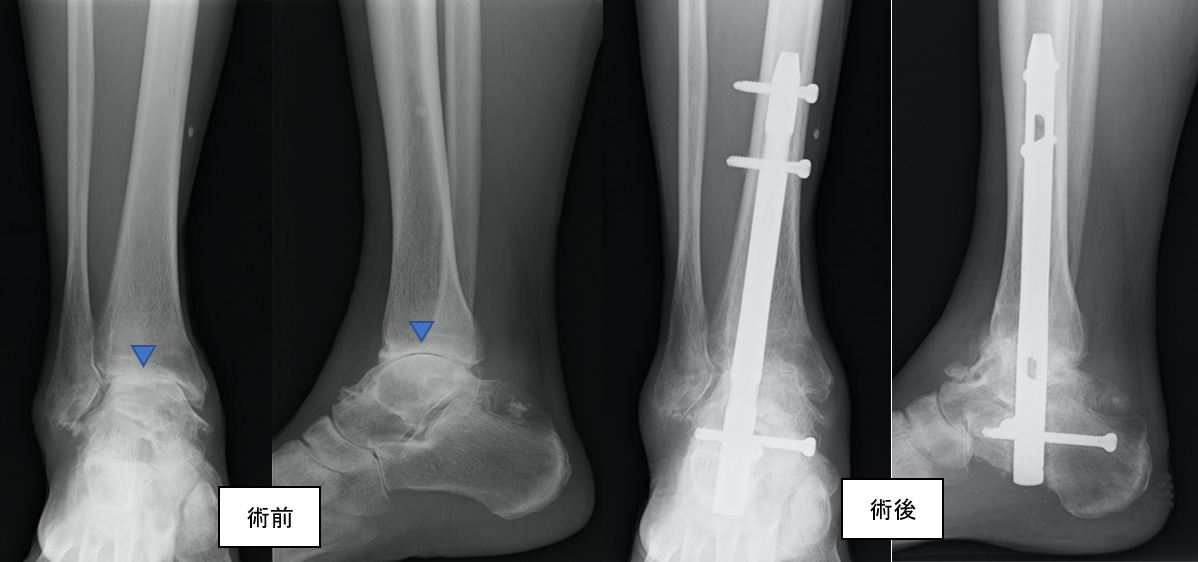

図3.変形性足関節症の固定術前後のX線画像。

術前では、軟骨のすり減りや変形によって関節の隙間がなくなっているのが確認できます(▲)。

術後は髄内釘によって関節が固定されています。